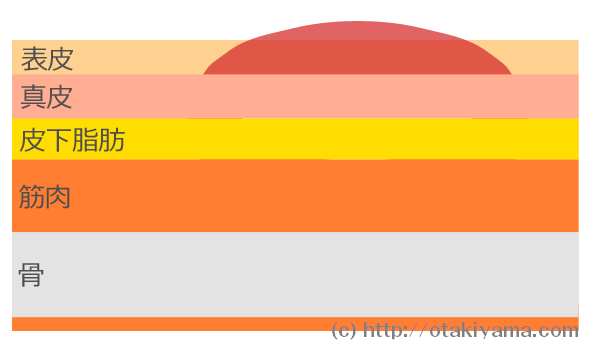

皮膚の観察褥瘡辞典 for MEDICAL PROFESSIONAL医療関係者向け情報マルホ株式会社。

皮膚の観察褥瘡辞典 for MEDICAL PROFESSIONAL医療関係者向け情報マルホ株式会社。